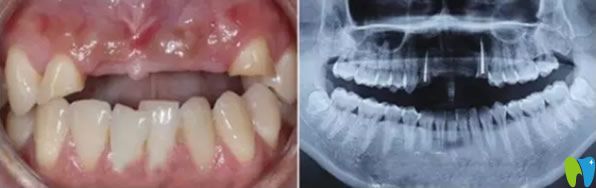

一次意外導(dǎo)致老公門牙缺失,在一家小診所做的烤瓷牙,這幾年用著還可以,但是前幾天發(fā)現(xiàn)牙齦萎縮很嚴(yán)重 ,明顯一個坑。三十出頭小伙子看著像四十多歲大叔,這可怎么辦?網(wǎng)上說牙齒缺失可以通過種植牙來修復(fù),我們也不知道有沒有年齡限制,老公都30多歲了還能做種植牙?成都瑞爾口腔在我們這的口碑挺不錯的,我就陪老公來咨詢。

來院后面診的是郝亦工醫(yī)生,詳細(xì)檢查后,說老公的門牙可以通過牙齒種植來修復(fù),同時也能改善牙齦萎縮的現(xiàn)狀。郝主任說種植牙沒有年齡限制,只要身體無疾病,都可以種植。

郝醫(yī)生通過醫(yī)學(xué)種植技術(shù),根據(jù)老公牙齒狀況設(shè)計(jì)種植方案。他將種植體與人體兼容性高的鈦金屬精準(zhǔn)植入缺牙區(qū)的牙槽骨內(nèi),等三個月后,人工牙和牙槽骨緊密結(jié)合,再做烤瓷牙、全瓷牙冠。郝醫(yī)生植入牙根手術(shù)完成后,老公從手術(shù)室出來牙齦看著就沒有之前那么憋了,飽滿了許多。